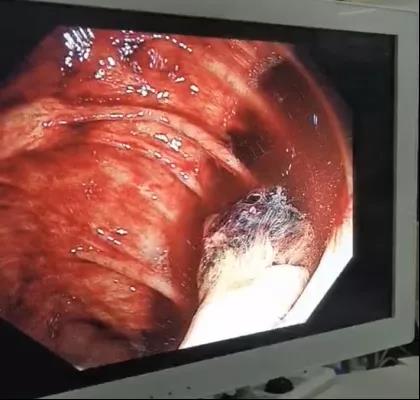

10月14日,患者无明显诱因出现暗红色血便,量约1900ml。通过多学科联合会诊,给予质子泵抑制剂、奥曲肽、反复输血等治疗。但患者仍有暗红色血便,每日50—100ml。7日后患者突然便血1300ml,呈暗红色,伴有血压下降,病情逐渐加重。重症医学科主任医师李冬纯按疑难危重患者的识别标准上报医务科组织全院MDT讨论,考虑下消化道出血,需进一步明确出血原因。经医务科协调,请内镜中心曹鹏副主任会诊,内镜团队4人至重症医学科为患者行床旁肠镜检查。镜下可见肠道内大量出血,反复冲洗肠道,终于在回盲部见“因创伤导致的该部位出血灶”,给予镜下电凝止血治疗。在随后的24小内患者无血便发生,生命体征趋于稳定。